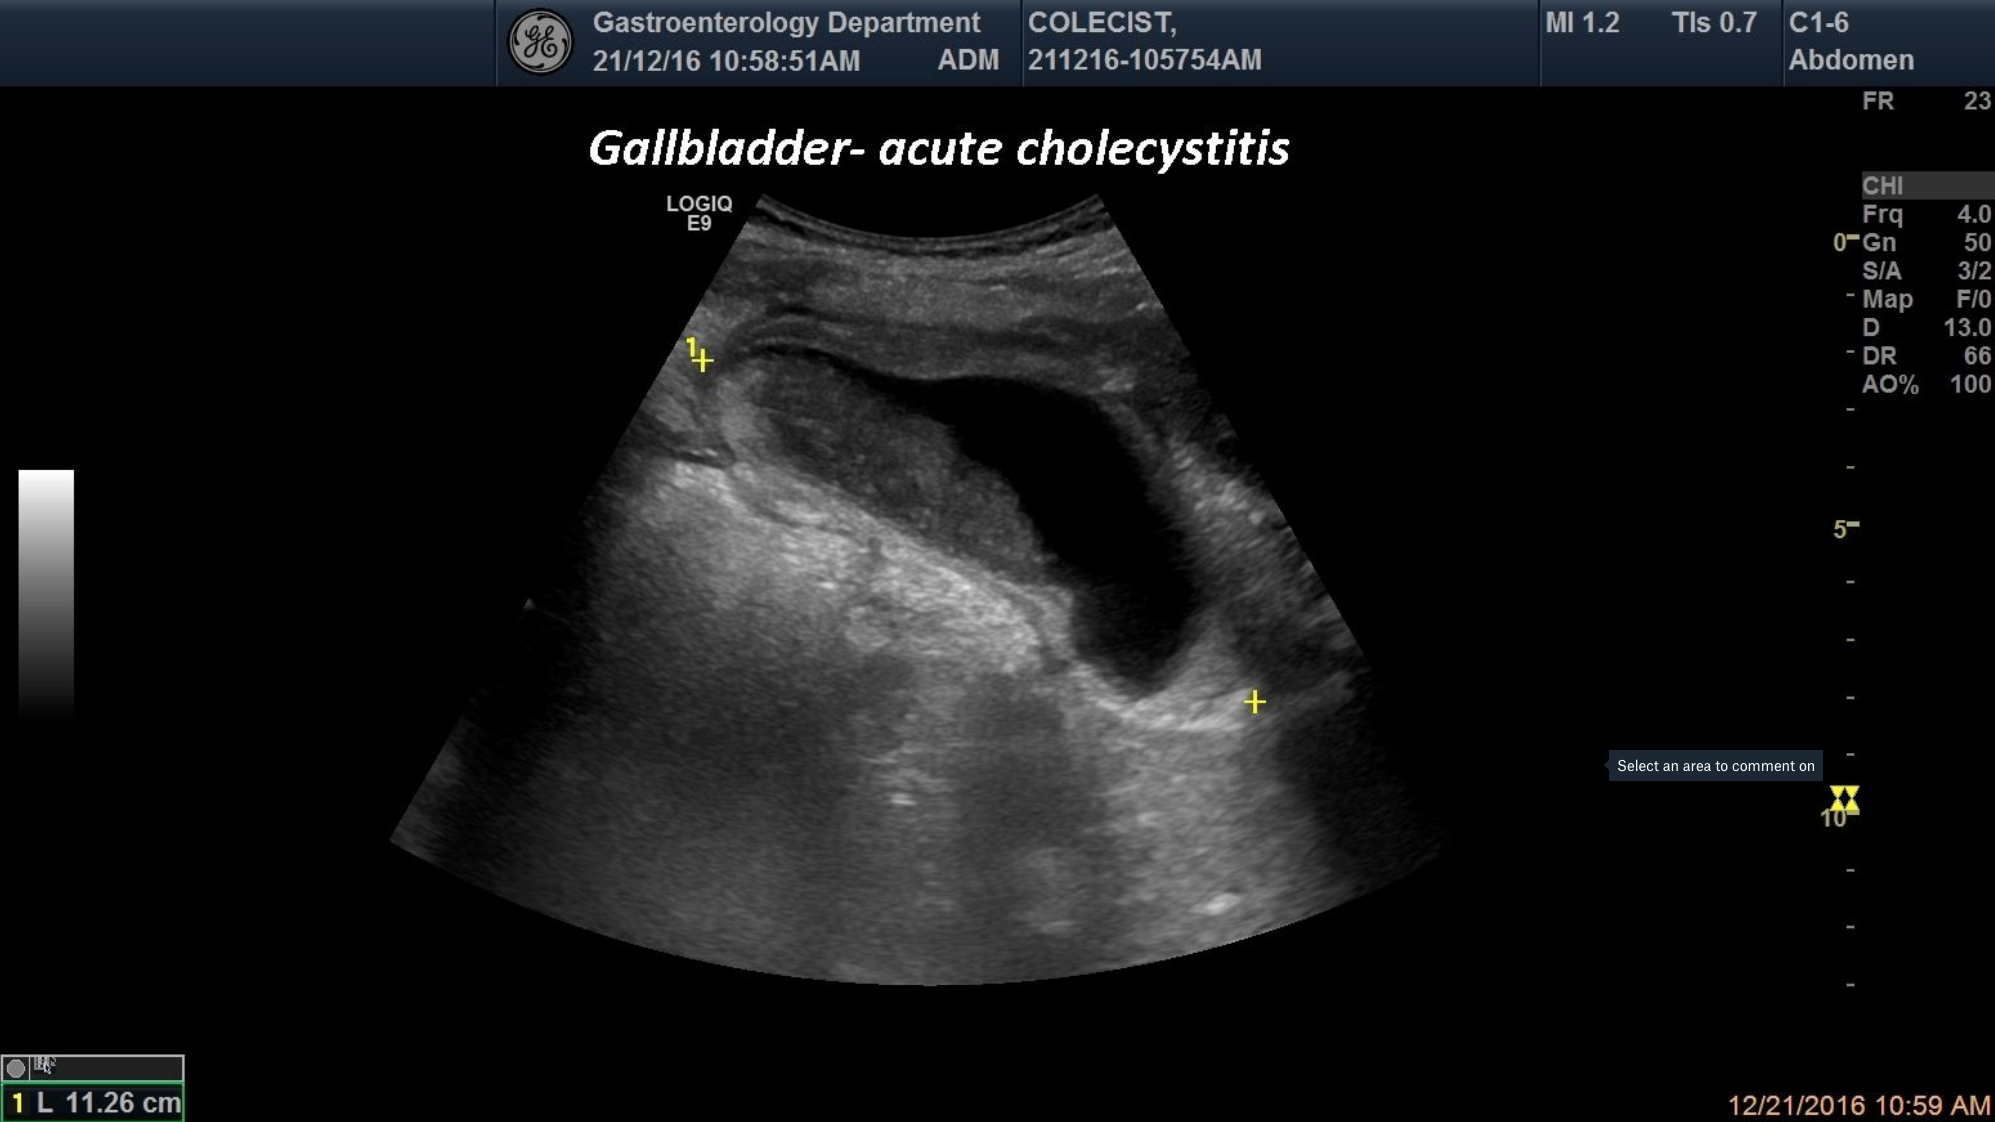

TITLE: Acute Cholecystitis

An 48-year-old patient was brought into the emergency room for acute abdominal pain located in the right upper quadrant. Ultrasound examination has revealed a distended gallbladder with thick and duplicated gallbladder walls and biliary sludge. The clinical and ultrasonographic signs are oriented towards the diagnosis of acute cholecystitis.